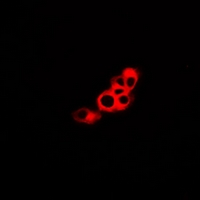

| WB, IF |

| Dilution | WB~~1/500 - 1/1000 IF~~1/50 - 1/200 |